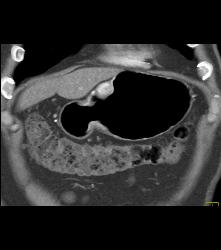

Glomus Tumor